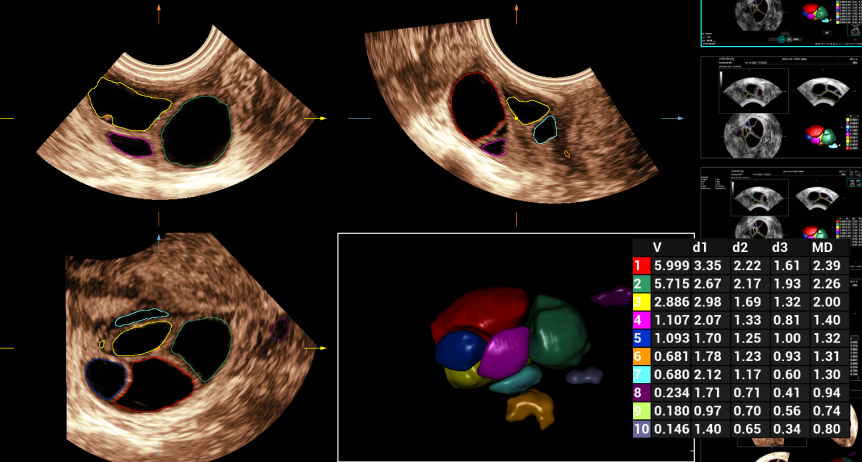

AUTO EF